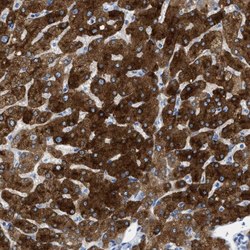

- Immunohistochemical staining of ASGR1 in human liver tissue shows strong positivity in hepatocytes. Samples were probed using an ASGR1 Polyclonal Antibody (Product # PA5-52994).

- Immunohistochemical staining of ASGR1 in human liver using ASGR1 Polyclonal Antibody (Product # PA5-52994) shows strong cytoplasmic positivity in hepatocytes.